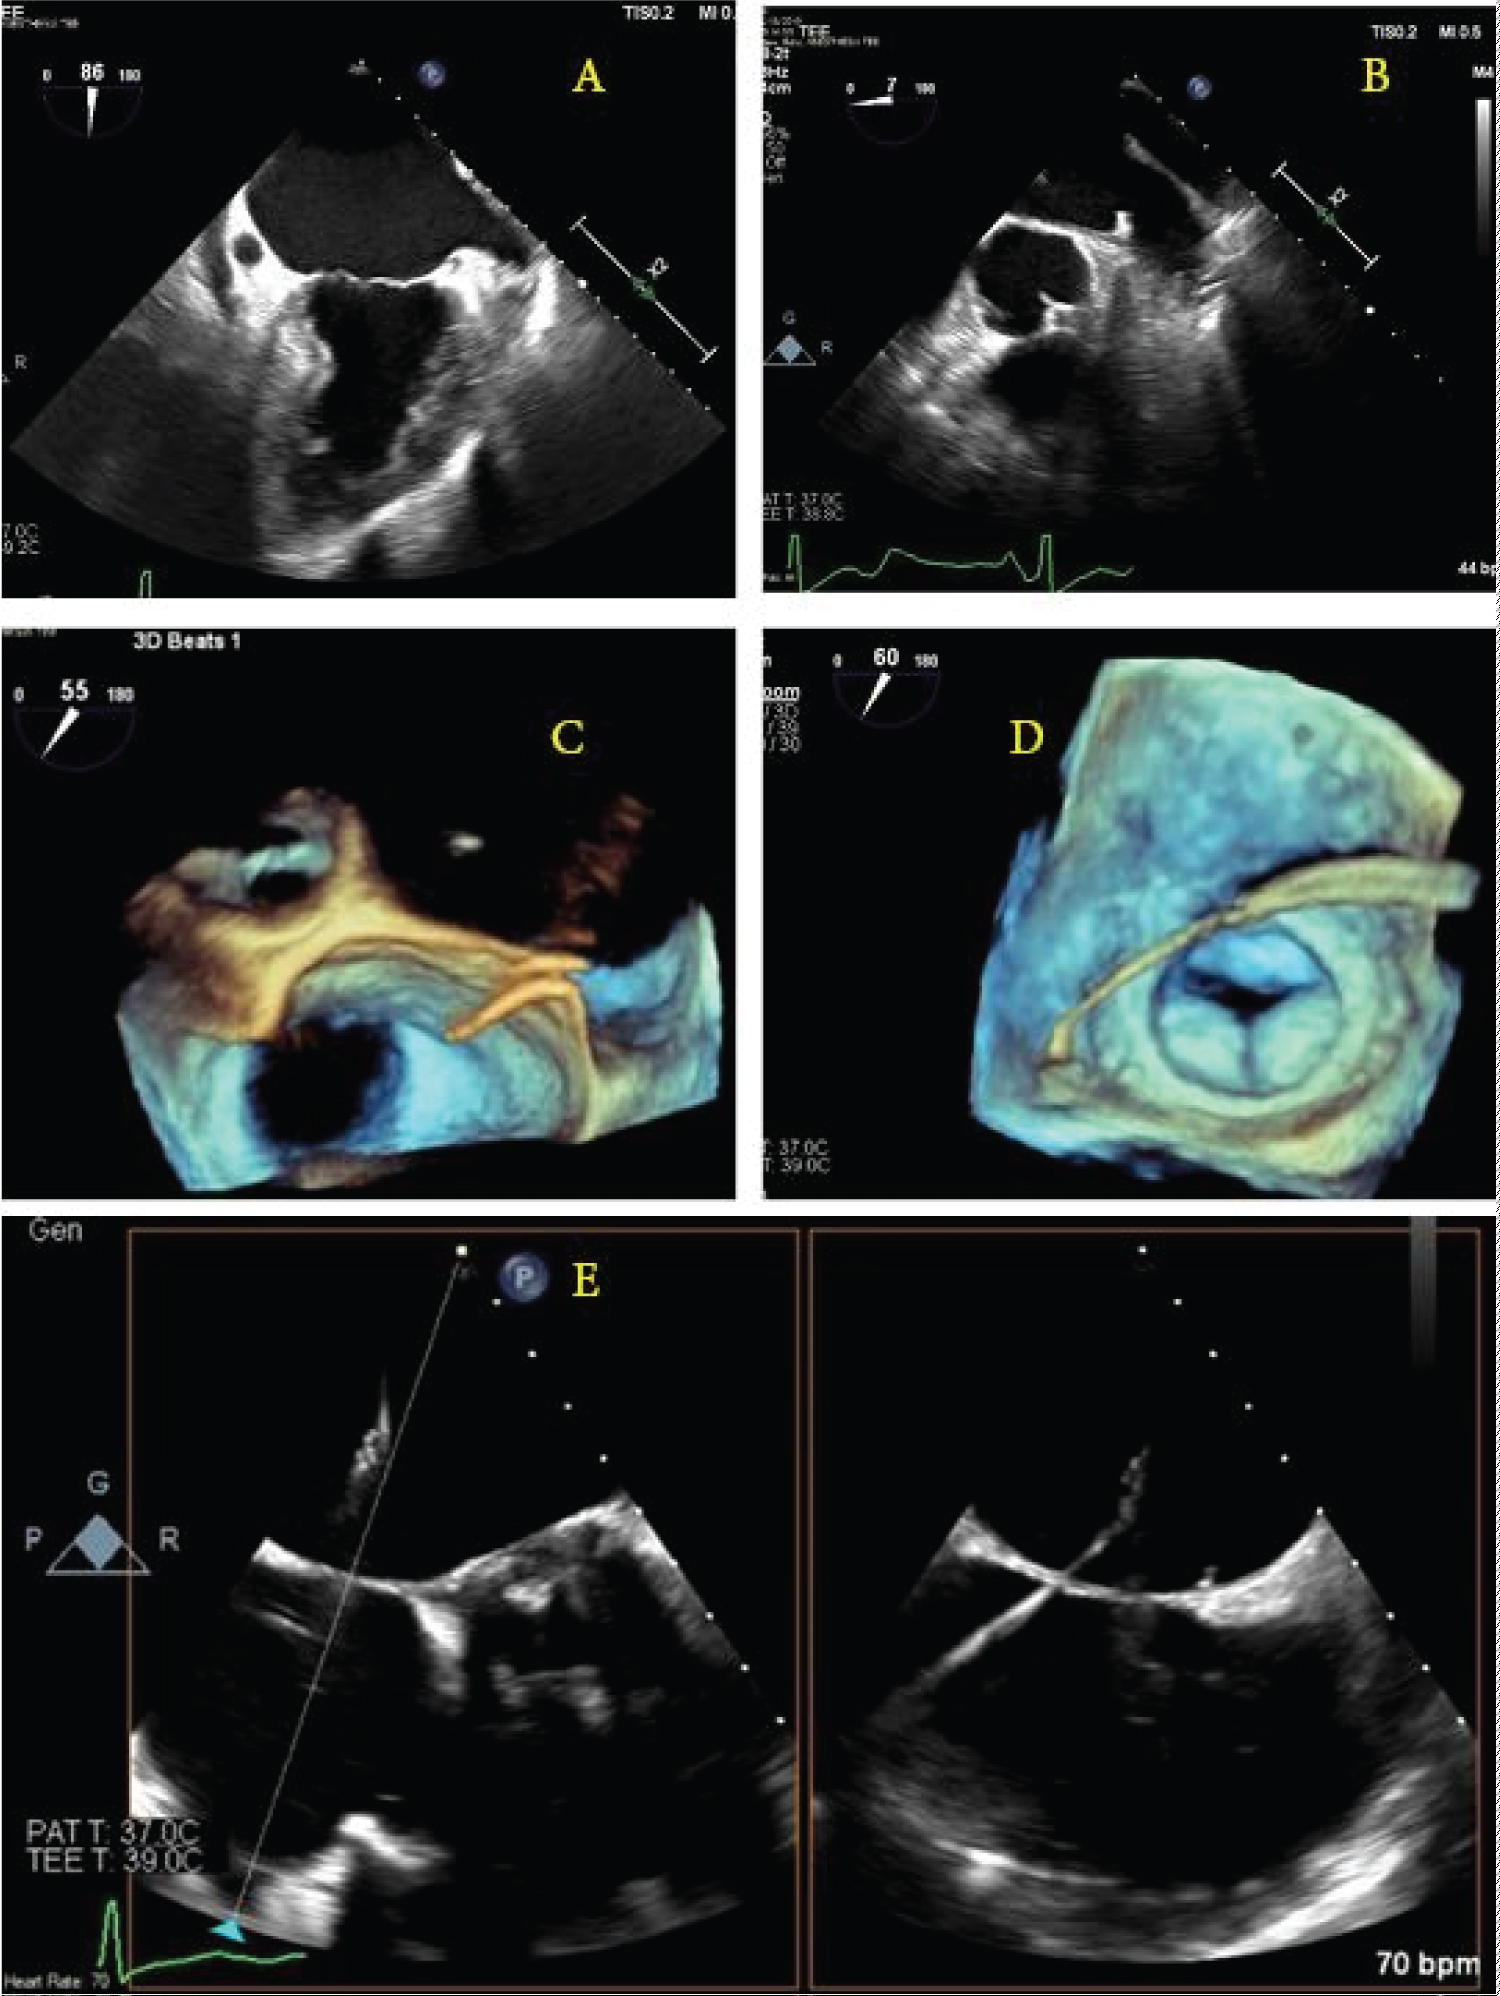

Expert-level use of intraprocedural TEE from either cardiology or anesthesia providers is crucial to success. The ability to supplement standard fluoroscopic views with real-time, multiplanar views of the anatomically complex LAA allows for a more complete map of ostium size, shape, depth, number of lobes, and position and correct sizing of devices. Per Mobius-Winkler, et al., the four ideal TEE views of the LAA include (a) A midesophageal (ME) four-chamber view at 0°, (b) A ME mitral commissural view at 60°, (c) A ME two-chamber view at 90°, and (d) A ME aortic valve long-axis view at 135°. A careful examination of each of these views should be undertaken to ensure guidewires and catheters are correctly positioned within the appendage at each step of the procedure [16]. X-plane and three-dimensional (3D) imaging can be helpful in selecting the appropriate location along the interatrial septum for the performance of transseptal puncture and guidance of wires for device delivery (Figure 1). After deployment, TEE can be used to evaluate leaking around seal devices, hemopericardium, pericardial effusion, tamponade, or right ventricular compression. Surgical treatments of AF continue to evolve. Unfortunately, the long-term prospective study results on LAA occlusion devices have been somewhat disappointing, with heterogeneous outcomes reported. The stroke prevention rate was only noninferior to oral anticoagulants, and procedures were associated with variable types of complications [15,17,18]. The recently developed Watchman FLX device has demonstrated encouraging short-term efficacy with a high degree of LAA sealing and low procedure compilation rates [19,20].

Figure 1: Schematic illustration of the guidewire punch location and direction under the direction of real-time transesophageal echocardiogram 2D/3D images. (a,b) The left atrial appendage as seen at 90° and 0°; (c) A 3D view of the wire coming across the interatrial septum; (d) A 3D image showing the wire crossing the left atrium and entering the left atrial appendage; (e) X-plane image-guidance of transseptal puncture.